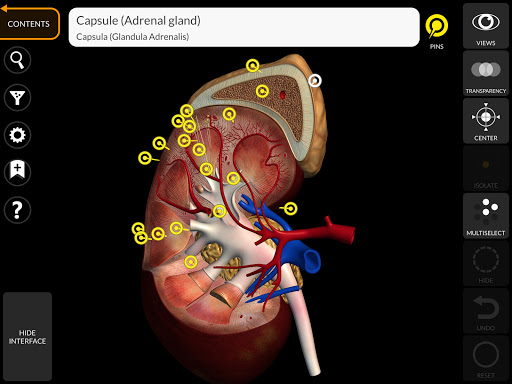

يتيح لك "Anatomy 3D Atlas" دراسة التشريح البشري بطريقة سهلة وتفاعلية.

من خلال واجهة بسيطة وبديهية، من الممكن ملاحظة كل بنية تشريحية من أي زاوية.

تتميز النماذج التشريحية ثلاثية الأبعاد بتفاصيل خاصة ودقة تصل إلى 4K.

يسهل التقسيم حسب المناطق والمناظر المحددة مسبقًا مراقبة ودراسة الأجزاء الفردية أو مجموعات الأنظمة والعلاقات بين الأعضاء المختلفة.

• الجهاز الصماء

• من خلال تحديد نموذج أو دبوس، يظهر المصطلح التشريحي ذي الصلة

• وصف العضلات: الأصل والإدخال والتعصيب والعمل